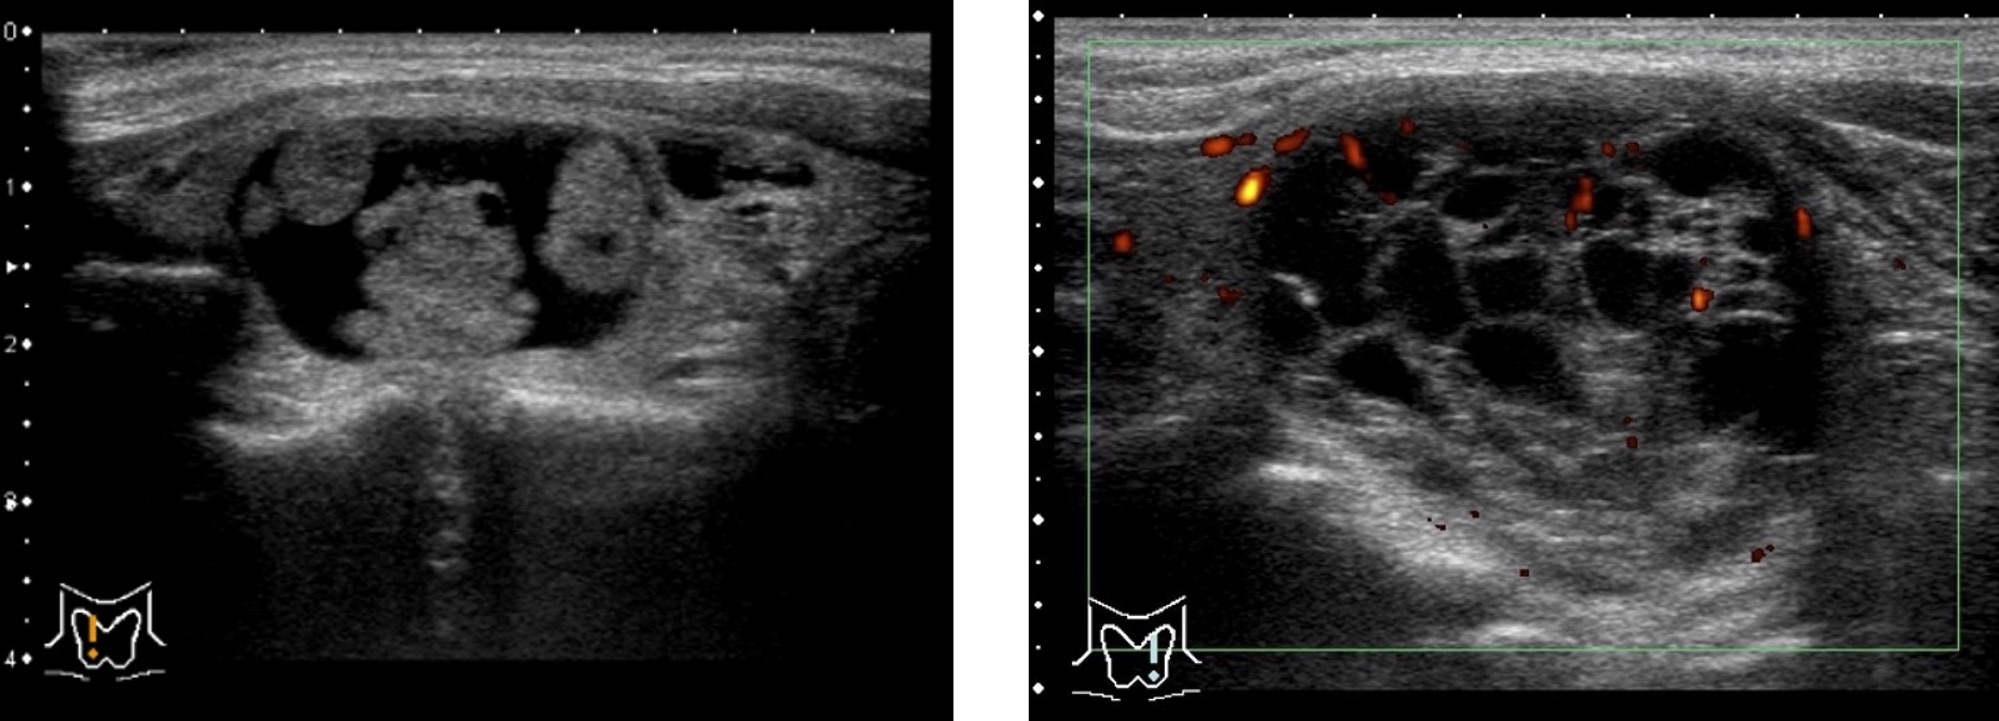

慢性甲状腺炎(橋本病)

慢性甲状腺炎(橋本病)甲状腺の表面がデコボコしています。

甲状腺全体が腫れて大きくなります。

甲状腺の内部が黒っぽくなり(エコーレベル低下)、むらがあります(内部不均質)。

※軽症の場合は正常な甲状腺とほとんど変わらない場合もあります。

亜急性甲状腺炎

痛みのある部位が黒く見えます(低エコー域)。